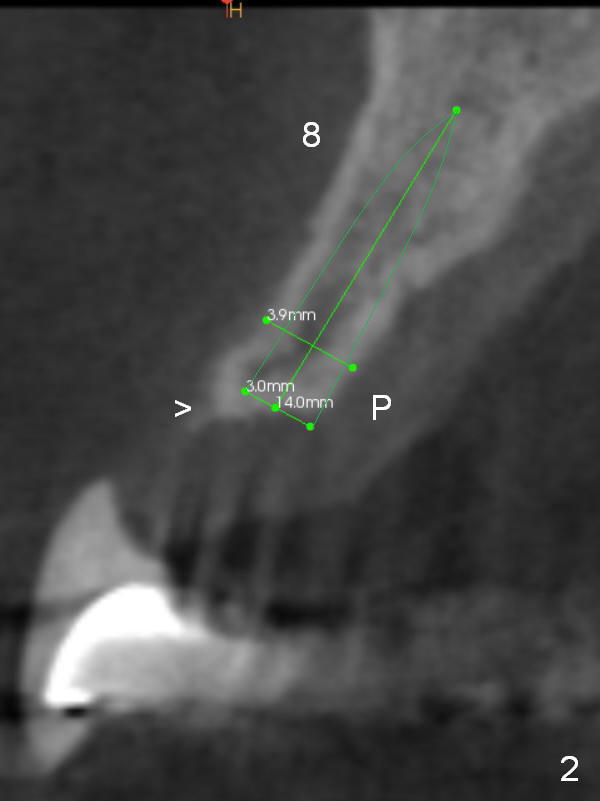

A 53-year-old man chips porcelain of the upper anterior bridge after implant placement at #14 and 15. Since he will return to home country for visit in the next few months, he is eager to restore the anterior restoration. Two of the abutments (#10, 11) appear to have severe bone loos (Fig.1,2 *). It does not seem to be a ideal treatment plan to redo the bridge. The edentulous ridge is atrophic at #8 and 9. It appears that 2.5 mm 1-piece implants (Fig.3,4) fit better than 3.0 mm one (Fig.2). There is a buccal concavity at #9 (Fig.1 red dashed line). The 2.5 mm implant at #9 should be placed between the Incisive Canal (Fig.1 I) and the buccal concavity (Fig.4). The ridge at the buccal concavity is not suitable for implant placement (Fig.5). The palatal plate (Fig.2 P) is usually denser and thicker than the buccal one. The osteotomy for the implant is initiated palatally; the implant is placed below the buccal crest (Fig.2 >). The exposed lingual thread will be covered by bone graft (Fig.3 pink circles) and collagen dressing. Since the ridge at #9 appears more atrophic, a 2.0 mm 1-piece implant may be indicated. The bridge will be sectioned between 7 and 8 and 9 and 10.